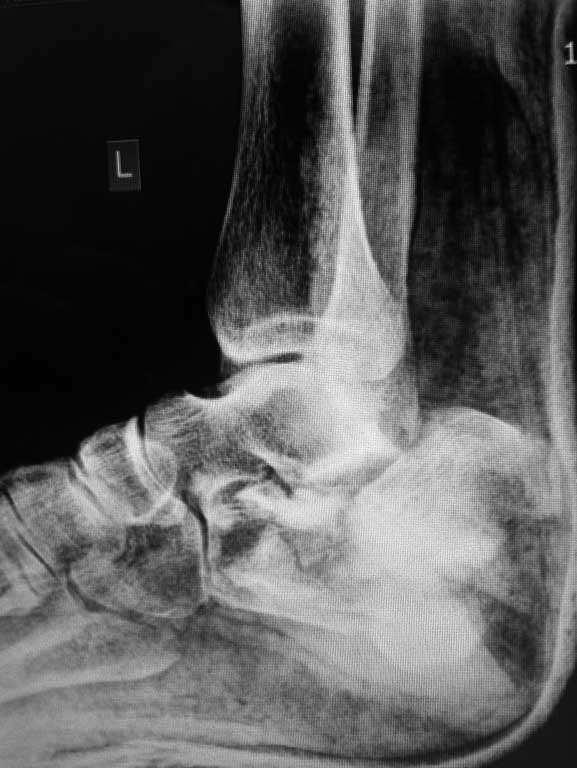

Представляю вашему вниманию следующий случай, интересуют ваши предложения по выбору метода оперативного лечения перелома пяточной кости.

Больной Н., 38 лет, к нам переведен из другого ЛПУ, травма менее недели назад, в результате ДТП, получил закрытый многооскольчатый перелом пяточной кости со смещением, так же есть на этой же конечности перелом шейки бедра(базальный). Интересует ваше мнение по поводу выбора оперативного метода?склоняемся к аппарату...